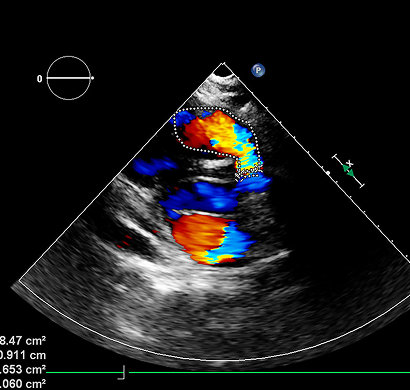

Echocardiography, commonly known as Echo, is a highly effective, non-invasive diagnostic test used to assess the structure and function of the heart. It utilizes advanced ultrasound technology to produce real-time images of the heart, enabling doctors to examine its chambers, valves, walls, and blood vessels in detail. This imaging helps evaluate how well the heart is pumping and ensures that blood is circulating properly throughout the body. Echo plays a crucial role in detecting a wide range of heart conditions. It helps identify valve disorders such as narrowing or leakage, heart muscle weakness, congenital heart defects, and conditions related to abnormal blood flow. It is also useful in diagnosing fluid buildup around the heart and other structural abnormalities that may affect overall cardiac performance.

One of the key advantages of Echo is that it is completely safe, painless, and does not involve any radiation exposure. The procedure is simple and usually takes around 15 to 30 minutes. During the test, a small handheld device called a transducer is gently moved over the chest to capture detailed images of the heart using sound waves. Echo is not only important for diagnosis but also for ongoing monitoring of heart conditions.